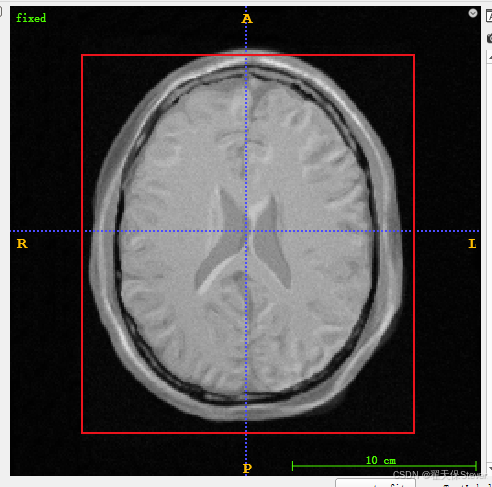

3)加载fixed.mhd成功如下所示。

4)点击File,点击Add Another Image,加载moving.mhd,如下所示。

5)在第二张图右上角有个箭头,点一下,选择Display as overlay,会发现第二张图像和第一张图像融合在一起了。